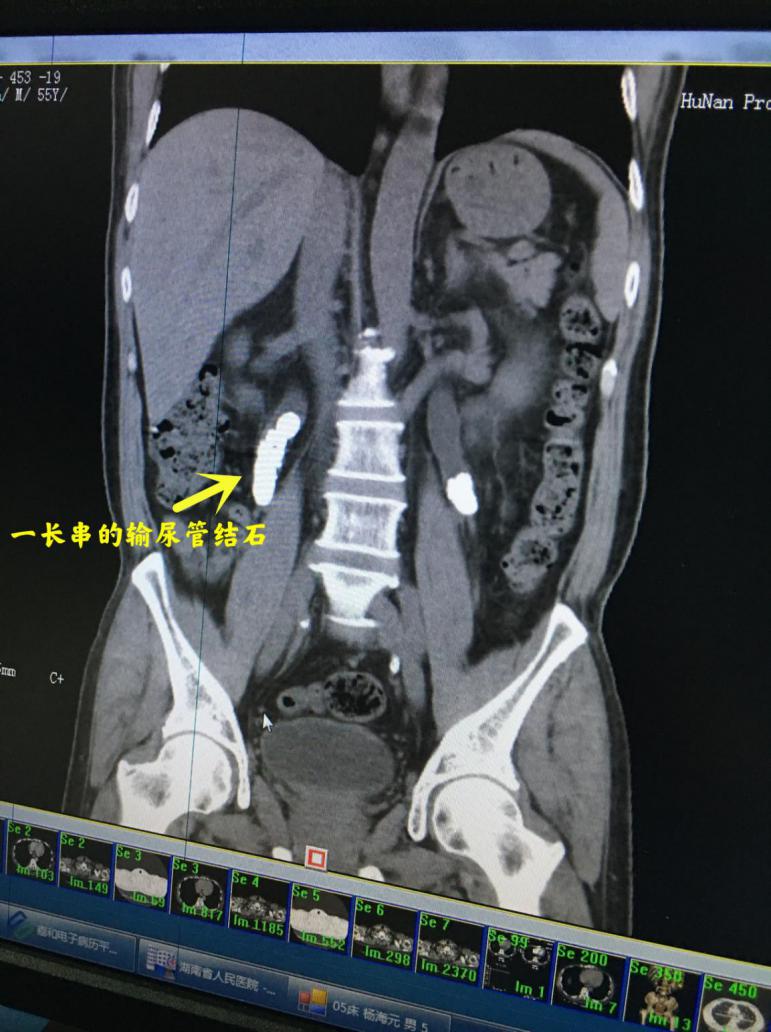

术中,医生发现,章大叔体内结石多且分布散,双侧输尿管和肾脏内都有多发结石,右侧输尿管内还形成了长石街,单纯的输尿管镜完全无法处理这类复杂的结石,只有通过经皮肾镜激光碎石取石的手术方式才可能将结石取净,取出来的结石像极了溪边鹅卵石,光滑且硬度很高。